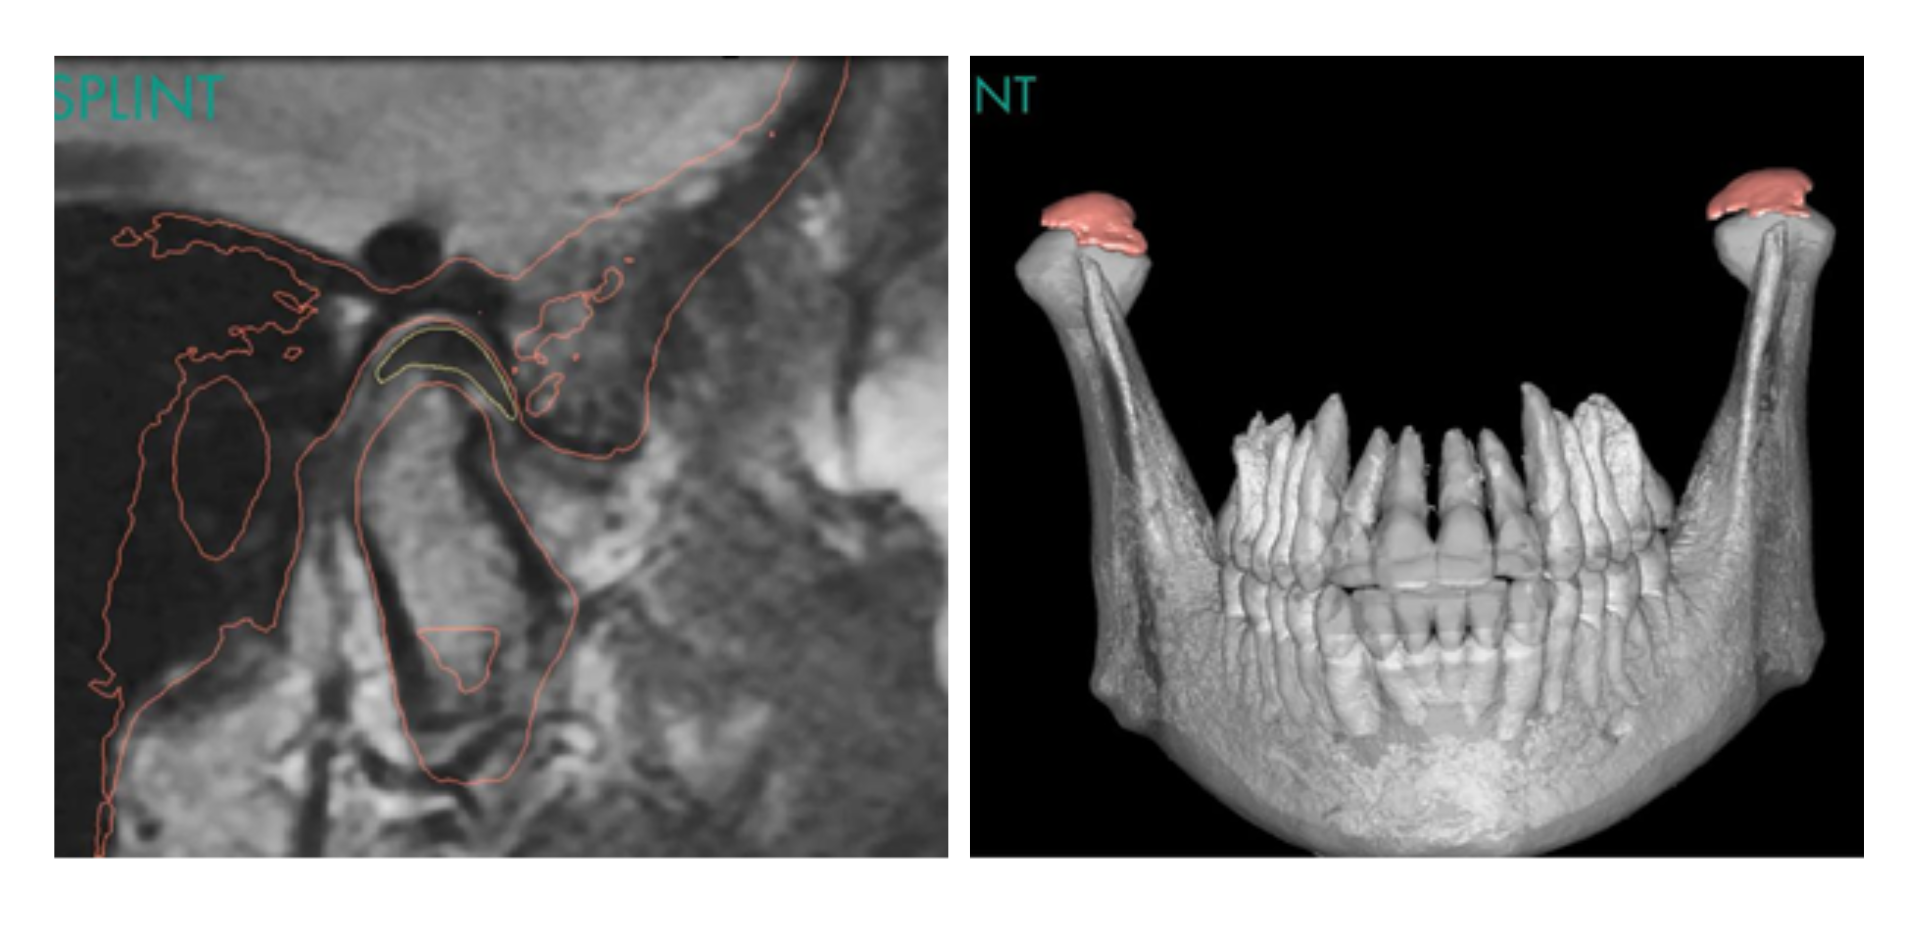

- Interpretar de forma avanzada la ATM mediante CBCT y RM.

• Articulación temporomandibular. Abordaje diagnóstico completo.

Sábado 16 de mayo (dos horas) - CBCT en la evaluación de la ATM, Dra. Ana Ortega

• Anatomía ósea de la ATM y variantes.

• Relación cóndilo–fosa mandibular.

• Análisis métrico del espacio articular.

• Cambios adaptativos vs degenerativos.

• Protocolo de informe radiológico con fines formativos.

Sábado 13 de junio (dos horas)- Resonancia magnética de la ATM, Dra. Adalsa Hernández

• Avances en Resonancia Magnética para el estudio de la ATM.

• Secuencias volumétricas, dinámicas y de difusión.

• Secuencia Bone y Mapeo T2.

• Integración RM–CBCT.

• Qué describir y cómo plasmarlo en el informe radiológico en contexto docente.